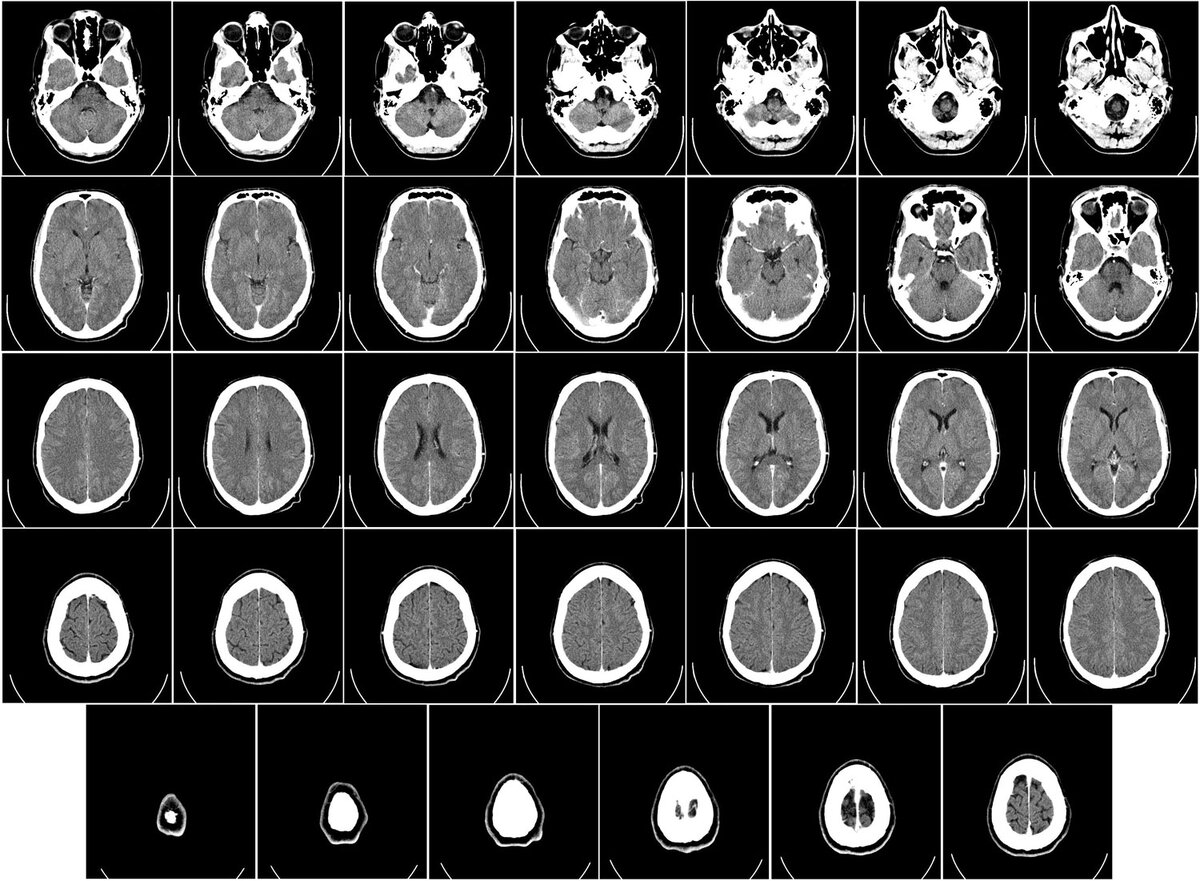

Норвежские ученые обнаружили, что на МРТ мозг рожавших женщин обычно выглядит моложе, чем у нерожавших. К такому выводу они пришли, изучив сканы мозга более 12 тысяч женщин. Разница была не такой уж большой — всего в несколько месяцев — однако этого оказалось достаточно, чтобы нейросеть определила, рожала женщина или нет.

В течение беременности организм женщины адаптируется под потребности плода — в том числе экономит на работе мозга. В этот период и у человека, и у других млекопитающих обнаруживается приторможенный нейрогенез и снижение объема мозга. После родов нейрогенез усиливается и мозговые структуры возвращаются к исходному состоянию. Можно предположить, что эти изменения не проходят бесследно и сказываются на дальнейшей работе мозга, в том числе и на темпах старения.

Как именно беременность и роды влияют на последующее старение мозга, до сих пор непонятно. Исследование норвежских ученых получилось скорее наблюдательным, никаких выводов о причинах различий между рожавшими и бездетными женщинами на его основании сделать невозможно.

Определять возраст мозга с помощью нейросетей геронтологи научились еще несколько лет назад. С тех, пор, например, они выяснили, что женский мозг в среднем на 3-4 года моложе мужского.